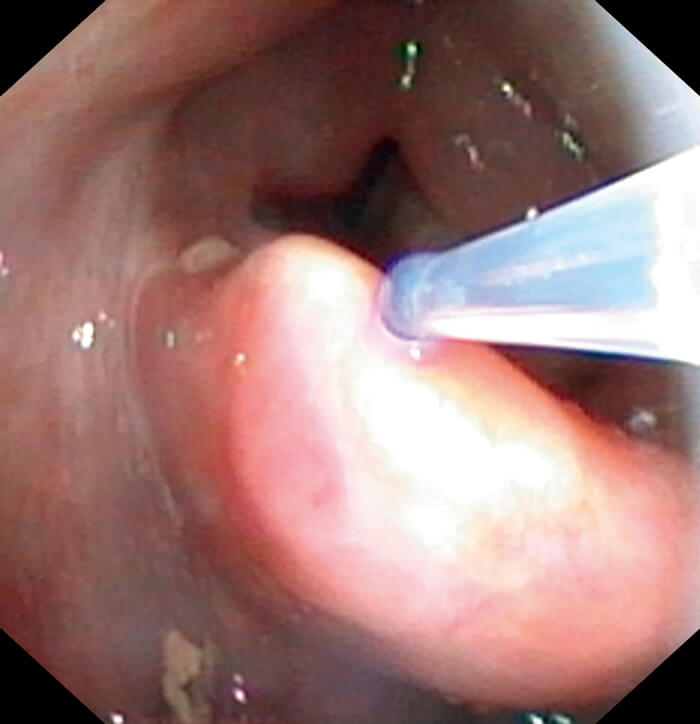

Drip catheter.

The procedure is performed in either the outpatient clinic or the ward treatment room with the patient sat in an examination chair. The nose is examined and the most appropriate side is then packed using cotton wool soaked in lignocaine and phenylephrine topical solution. This is left in-situ for 10 minutes. The packing is removed and the ported scope is introduced. Further topical anaesthesia is administered via an epidural catheter placed down the endoscope channel. This allows further administration of 1-2% lignocaine under endoscopic guidance to the nasopharyngeal surface of the soft palate and the larynx.

The patient is instructed to make a prolonged ‘e’ sound to allow laryngeal gargling of the topical anaesthetic if the vocal folds are to be biopsied. After visualisation of the lesion, biopsies are performed using the flexible biopsy forceps (EndoJawTM Alligator jaw-step fenestrated 1.9mm FB-211D, Olympus Medical Systems Corp, Japan) which are passed down the endoscope channel. The biopsies are taken under endoscopic guidance by pushing the open jaws into the lesion, closing the jaws and pulling back swiftly on the forceps whilst holding the endoscope steady.